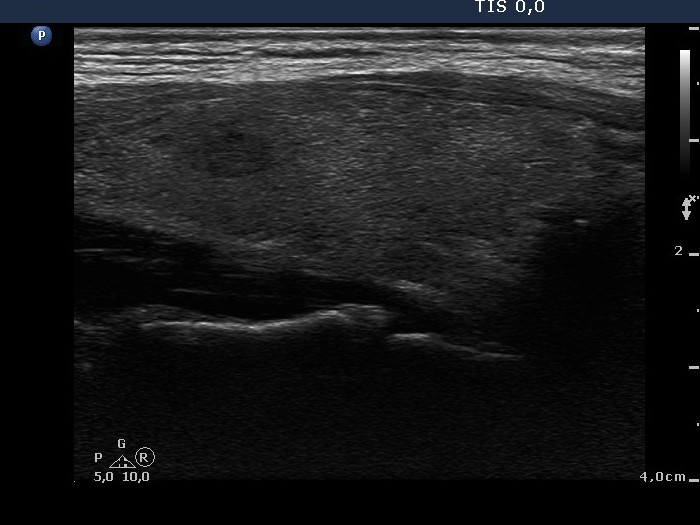

Lymph nodes - case conp 005 (ultrasonographic picture 2)

Right lobe, longitudinal scan.